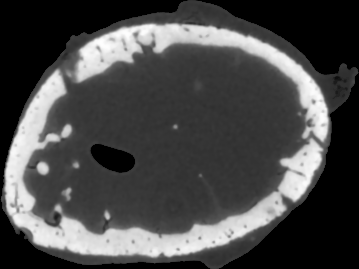

To test the proposed penalty in regularized tomographic reconstruction we designed an analytical phantom which consists of a smooth (two Gaussians and two parabolas) and piecewise-constant (one rectangle) functions (see Fig. 1).

To avoid of reconstructing on the same grid where projection data was generated (so-called reconstruction with “inverse crime” [16]), we used a higher resolution of the phantom on a isotropic pixel grid to generate projections with a strip kernel [1]. Then Poisson distributed noise was applied to the projection data, assuming an incoming beam intensity of 3 (photon count). Reconstructions were calculated on a isotropic pixel grid and with a linear projection model [1]. We used 90 projection angles in 180 degrees (assuming a parallel beam geometry) to reconstruct the phantom.

To simulate emission tomography reconstruction we designed a more realistic phantom from the high-quality X-ray scan of a mice bone. The data was acquired on a Nikon Metris Custom Bay cone-beam scanner at the Henry Moseley Manchester X-ray facility, and was reconstructed with the Feldkamp algorithm (see Fig. 7 (left)). We thresholded the obtained reconstruction and added six gaussians with various kernel widths (see Fig. 7 (middle and right)).